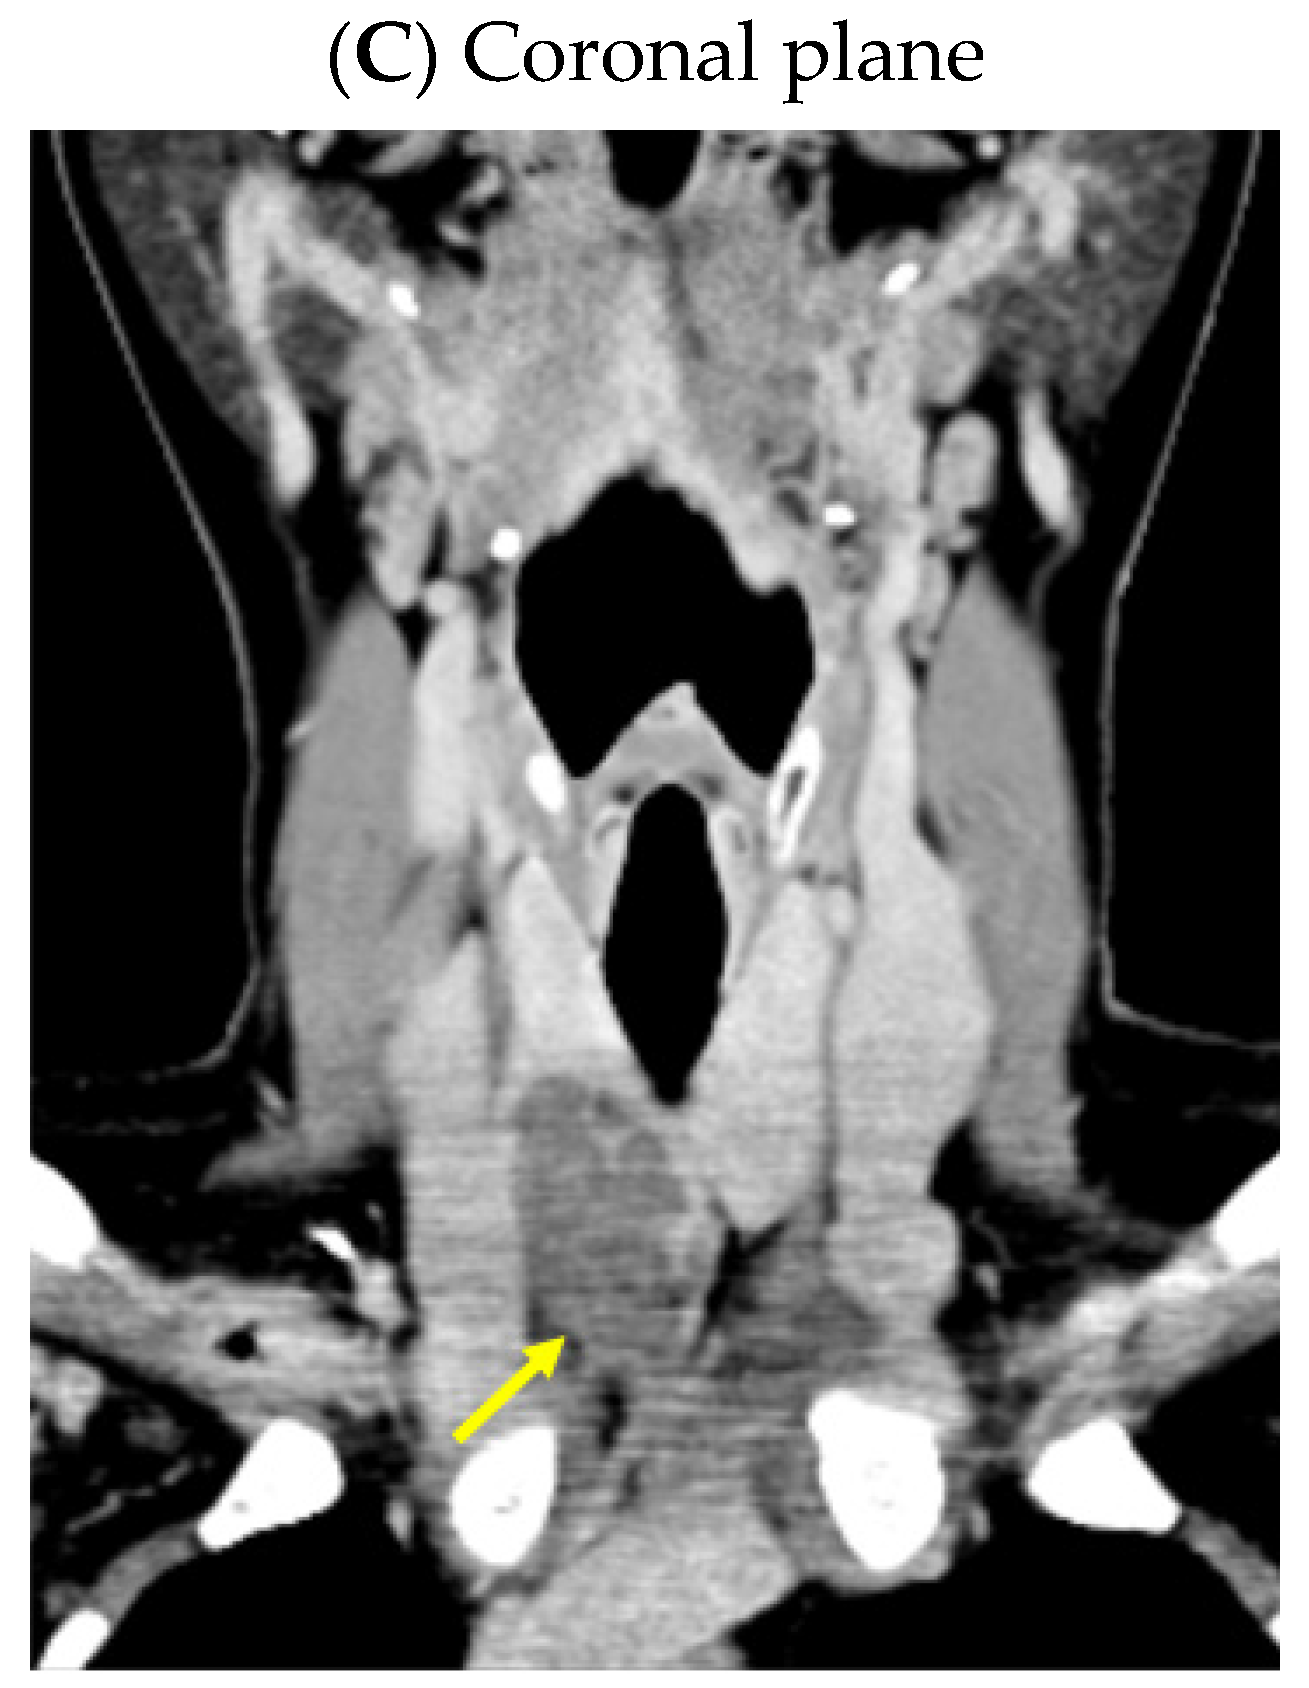

3.5. Outcome

Despite recommendations, she proved poorly compliant once again, and she was re-admitted only seven months later when she suffered a spontaneous fracture at the second cervical vertebra that required immobilization with a cervical collar. Amid this novel hospitalization, the PTH levels remained high with a reduced alkaline phosphatase level (Table 4). A native spine CT revealed an odontoid fracture involving the C1 anterior arch, also confirmed with a native magnetic resonance imaging (MRI) evaluation. Moreover, other left intramaxillary bone lesions were discovered. In this context, the examinations were extended to the level of the skeleton, and the head-thorax-abdomen-pelvis CT scan with intravenous contrast revealed multiple lesions located at different levels, such as the skull (of 3.5 by 3.8 cm), sternum (of 2.9 cm), sacrum (of 4 by 5.5 cm), and pelvis (of 6.5 by 5.5 cm) (Figure 12).

Figure 12.

Brown tumors in an adult lady with poorly controlled renal hyperparathyroidism. (A) Native craniocerebral magnetic resonance imagery (the lesions are highlighted as well as their largest diameter). (B) Intravenous contrast computed tomography showing the mentioned lesions (yellow arrow) at the level of the skull (left) and spine (right).